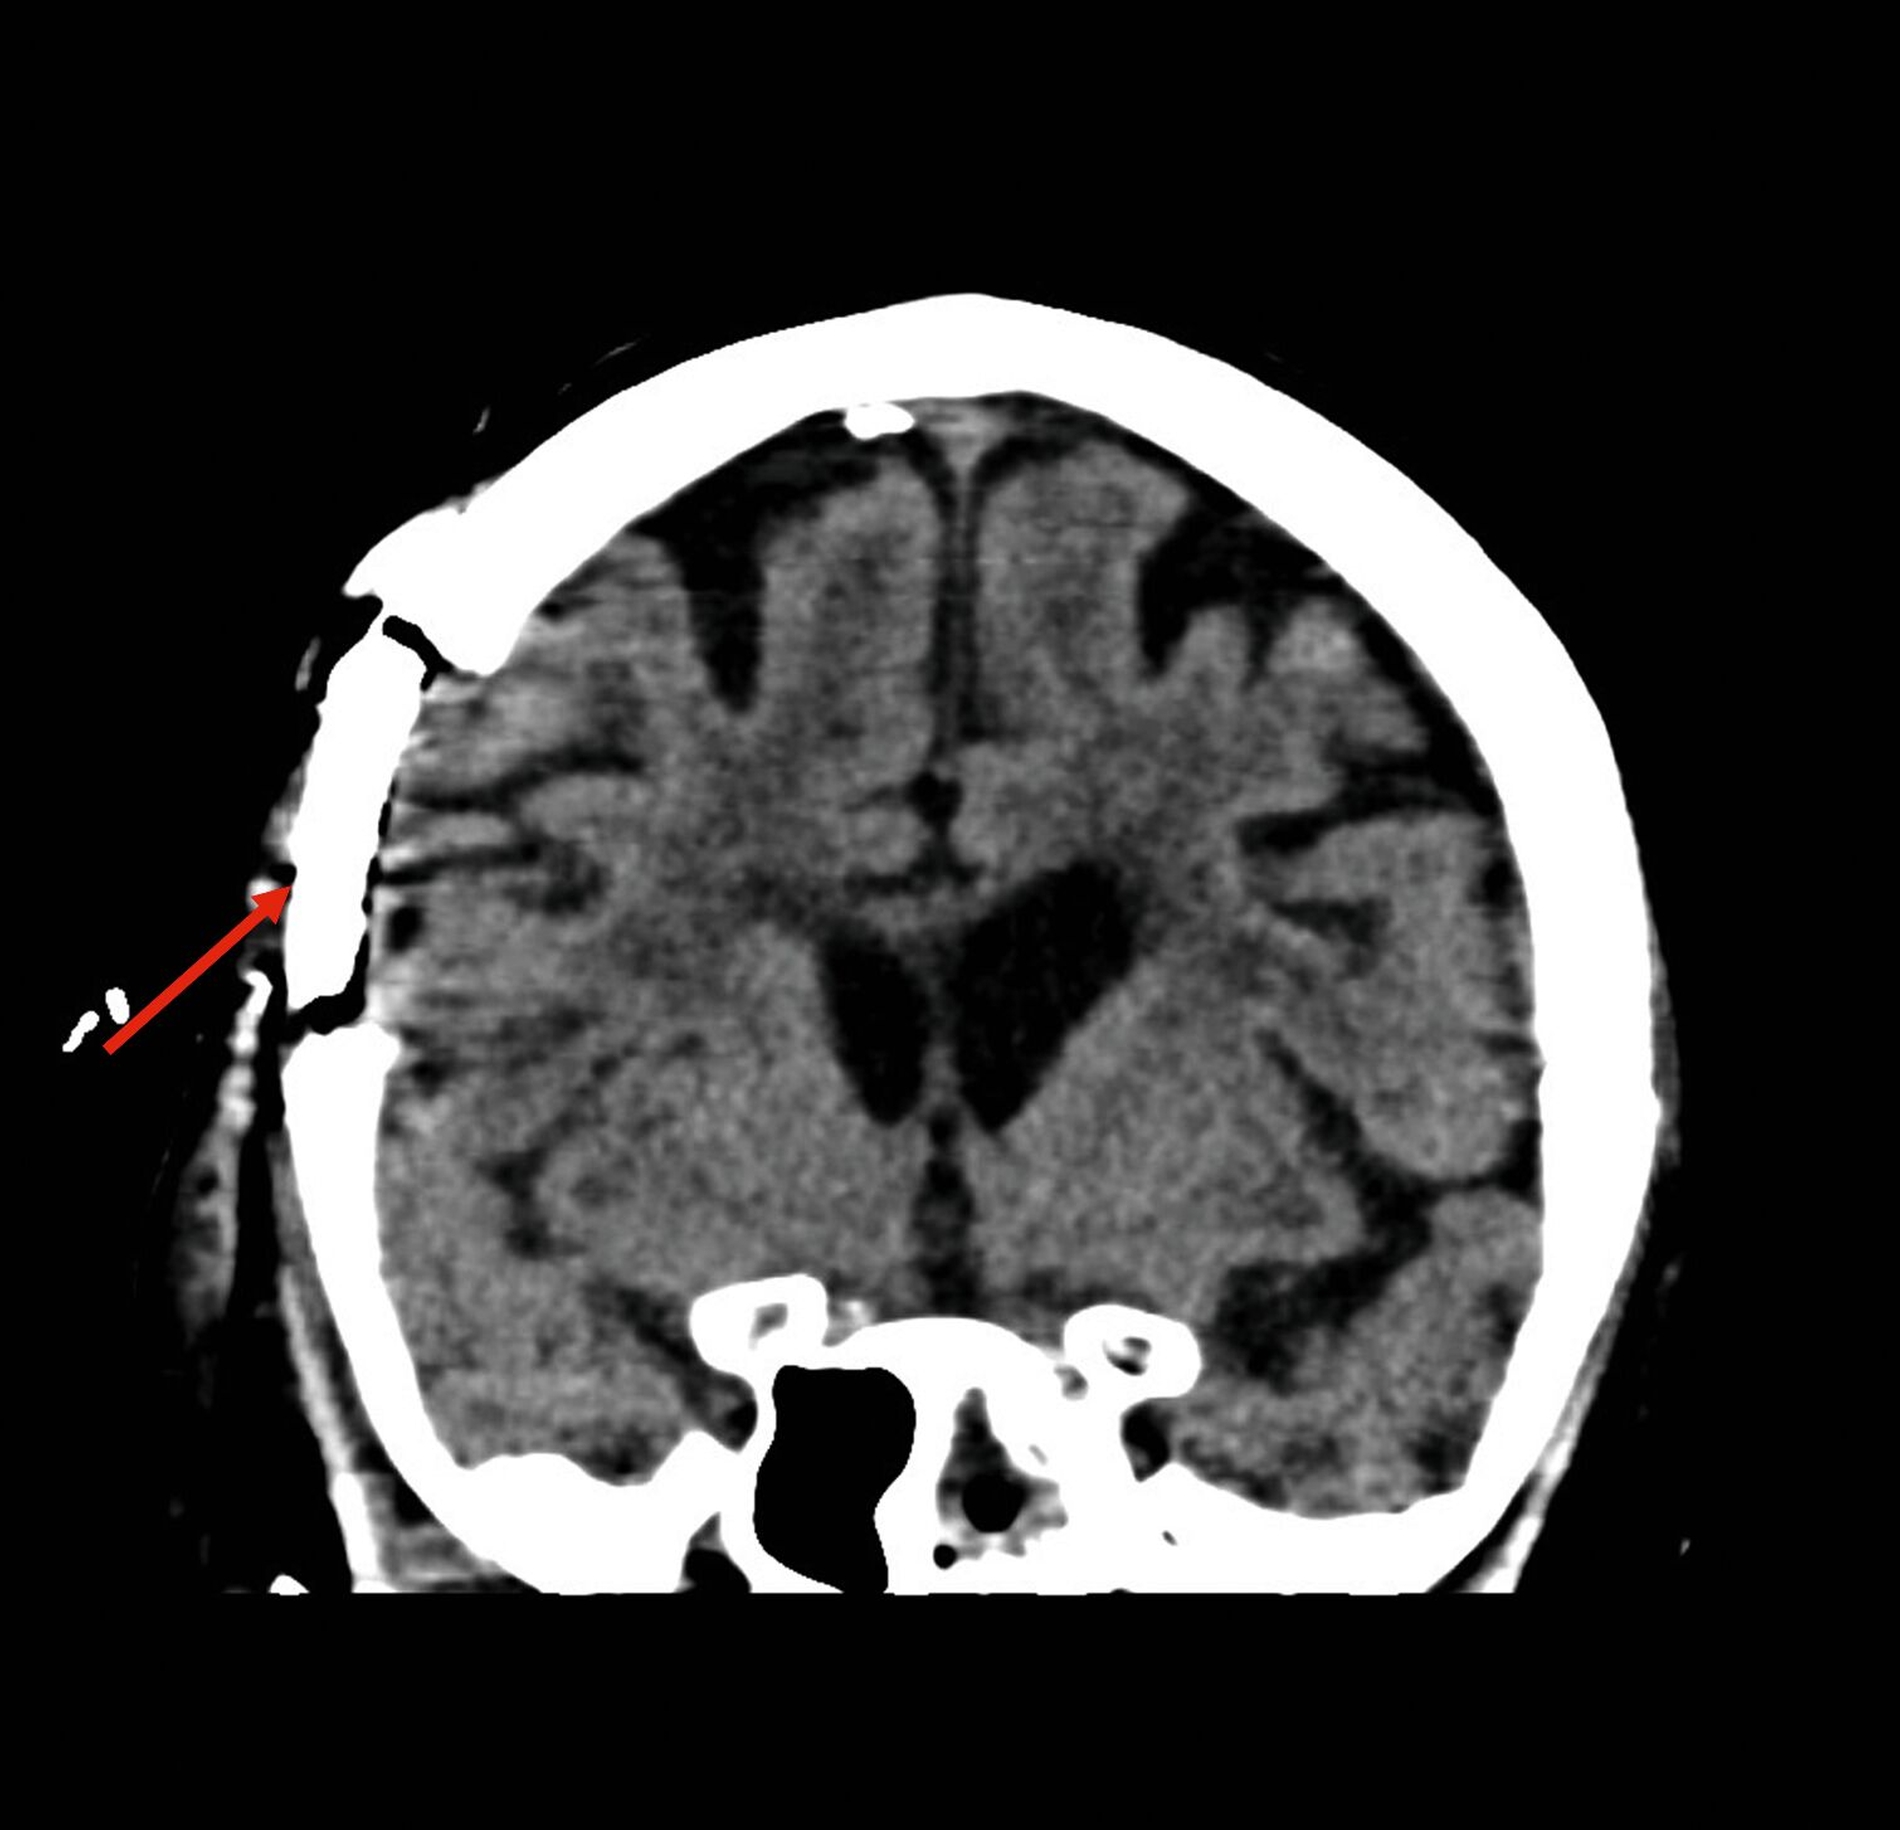

Im weiteren stationären Verlauf fiel am neunten postoperativen Tag eine zunehmende Somnolenz mit Wortfindungsstörungen und Wesensveränderung auf. Die zerebrale Schnittbildgebung zeigte eine hyperintense Läsion temporal rechts mit Verdacht auf einen zerebralen Abszess sowie eine Verschattung im Sinus sphenoidalis (Abbildung 3). Am selben Tag erfolgte durch die Kollegen der Neurochirurgie eine osteoplastische Kraniotomie mit Drainage des Hirnabszesses sowie eine Drainage des Keilbeinsinus durch die Kollegen der HNO (Abbildung 4). In beiden Lokalisationen wurde erneut Streptococcus intermedius als dominierende Bakterienspezies identifiziert – mit Resistenz gegenüber Clindamycin, jedoch guter Empfindlichkeit gegenüber Ampicillin.